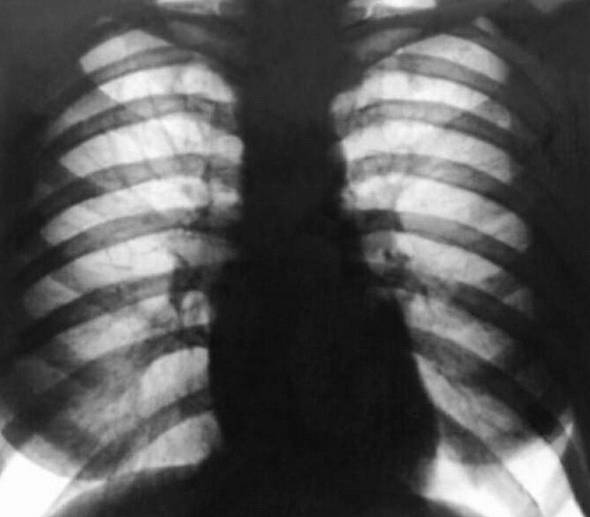

Остается незаменимым и рентгенологическое исследование. Внимательный динамический осмотр пациента при рентгеноскопии позволяет рассмотреть все детали развившейся патологии.

Рентгенологическую картину заболевания формируют увеличенные камеры сердца, смещение положения и видимые явления застоя в лёгких. Добавочные данные при диагностике порока митрального клапана дает электрокардиография.